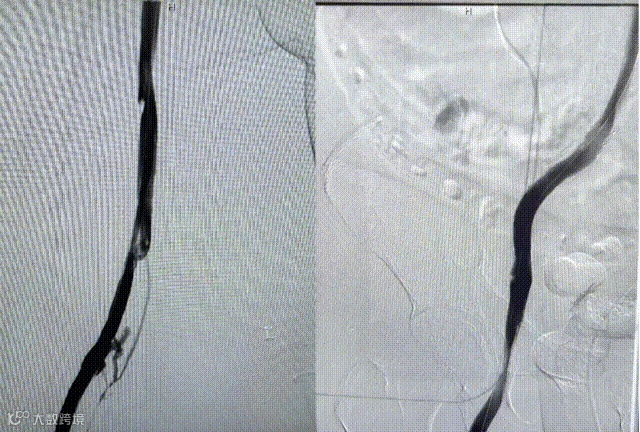

(一)患者取平卧位,常规消毒铺巾,右侧腹股沟区 1%利多卡因局部麻醉,Seldinger法穿刺右侧股静脉,置入6F 的血管鞘,导丝配合单弯导管至下腔静脉下端,经血管鞘造影,下腔静脉通畅,未见血栓形成。

(二)导丝交换置入长鞘,推送入腔静脉可回收滤器,路图模式下定位于肾静脉下缘释放滤器,再次造影见滤器形态位置满意。超声引导下穿刺左腘静脉成功,置入10F导管鞘,经鞘导入泥鳅导丝及单弯导管,反复尝试到达下腔静脉。

(三)导入大腔吸栓导管,经腘静脉吸栓至股总静脉,吸出大量血栓,造影后栓塞血管开通。

(四)导入球囊(10*80mm)扩张髂股静脉,再次造影见髂总静脉闭塞

(五)导入支架(14*90mm)覆盖髂总静脉压迫处,再次造影见髂股静脉通畅。拔除导管及导管鞘,术中出血约 300ml,术后患者安返病房。

造影可见:髂静脉 和股静脉血流复通